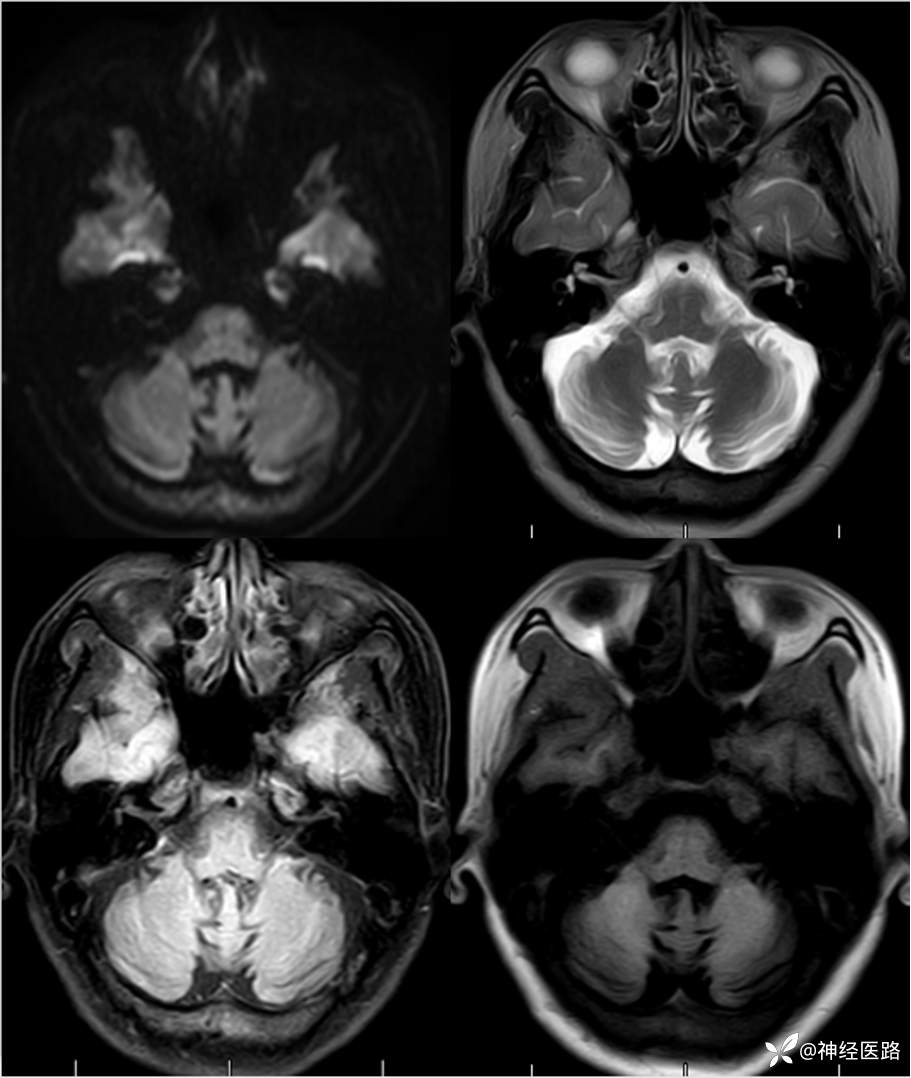

辅助检查:头部磁共振: 1.左侧额叶及右侧顶叶白质内高信号,请结合临床及相关检查。2.双侧小脑半球脑萎缩。3.部分颅骨信号增高。